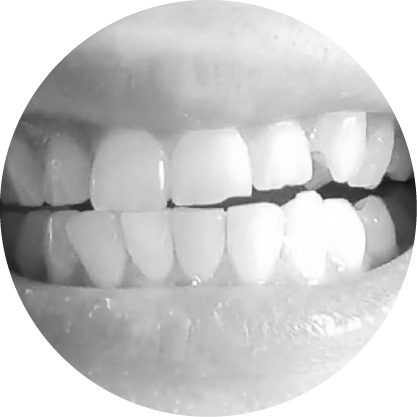

การสบฟันแบบเปิด (Anterior Open Bite)

การปิดช่องว่างระหว่างฟัน เพื่อการสบฟันที่มีประสิทธิภาพ

การสบฟันแบบเปิด โดยเฉพาะการสบฟันแบบเปิดด้านหน้าซึ่งฟันหน้าไม่สัมผัสกัน อาจส่งผลต่อการรับประทานอาหารและการพูด การแก้ไขทางทันตกรรมจัดฟัน จะเน้นที่การจัดฟันให้เรียงตัวกันใหม่เพื่อปิดช่องว่างและฟื้นฟูกลไกการสบฟัน ที่เหมาะสม

ตัวอย่างในชีวิตจริง